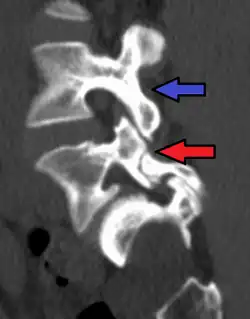

Red arrow brake in pars interarticularis. Blue arrow normal pars interarticularis. Spondylolisthesis at L5.

Cross-sectional image of a vertebra showing spondylolysis.

Commonly known as a CT Scan or CAT scan, this form of imaging uses x-rays to produce multiple cross-sectional images, or "slices", through a part of the body. This allows a physician to evaluate the body in greater detail than an x-ray allows. For this reason the CT scan is much more accurate in detecting spondylolysis than an x-ray. Bone scintigraphy combined with CT scan is considered the reference standard, which means that it is best at detecting spondylolysis.[16][18]